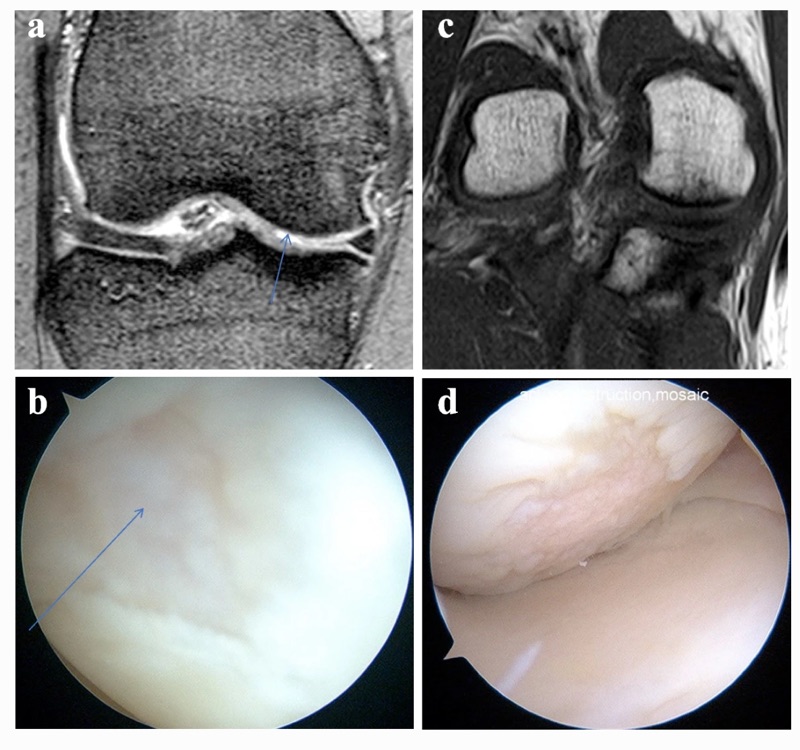

上圖:核磁共振下看到輕微的軟骨缺損,但做關節鏡下,卻看到軟骨已經是第四期的破裂變化.

膝關節的「軟骨破損」,在核磁共振下可能根本看不出來!

🔹 但一些表層磨損、細微破裂或髕骨後方滑車面的破損,常常容易被忽略

🔹 特別是如果損傷範圍小、沒明顯水腫,即使你很痛,影像還是可能「正常」!

許多病人一進行關節鏡才驚覺:「原來我的軟骨早就破得一塌糊塗!」